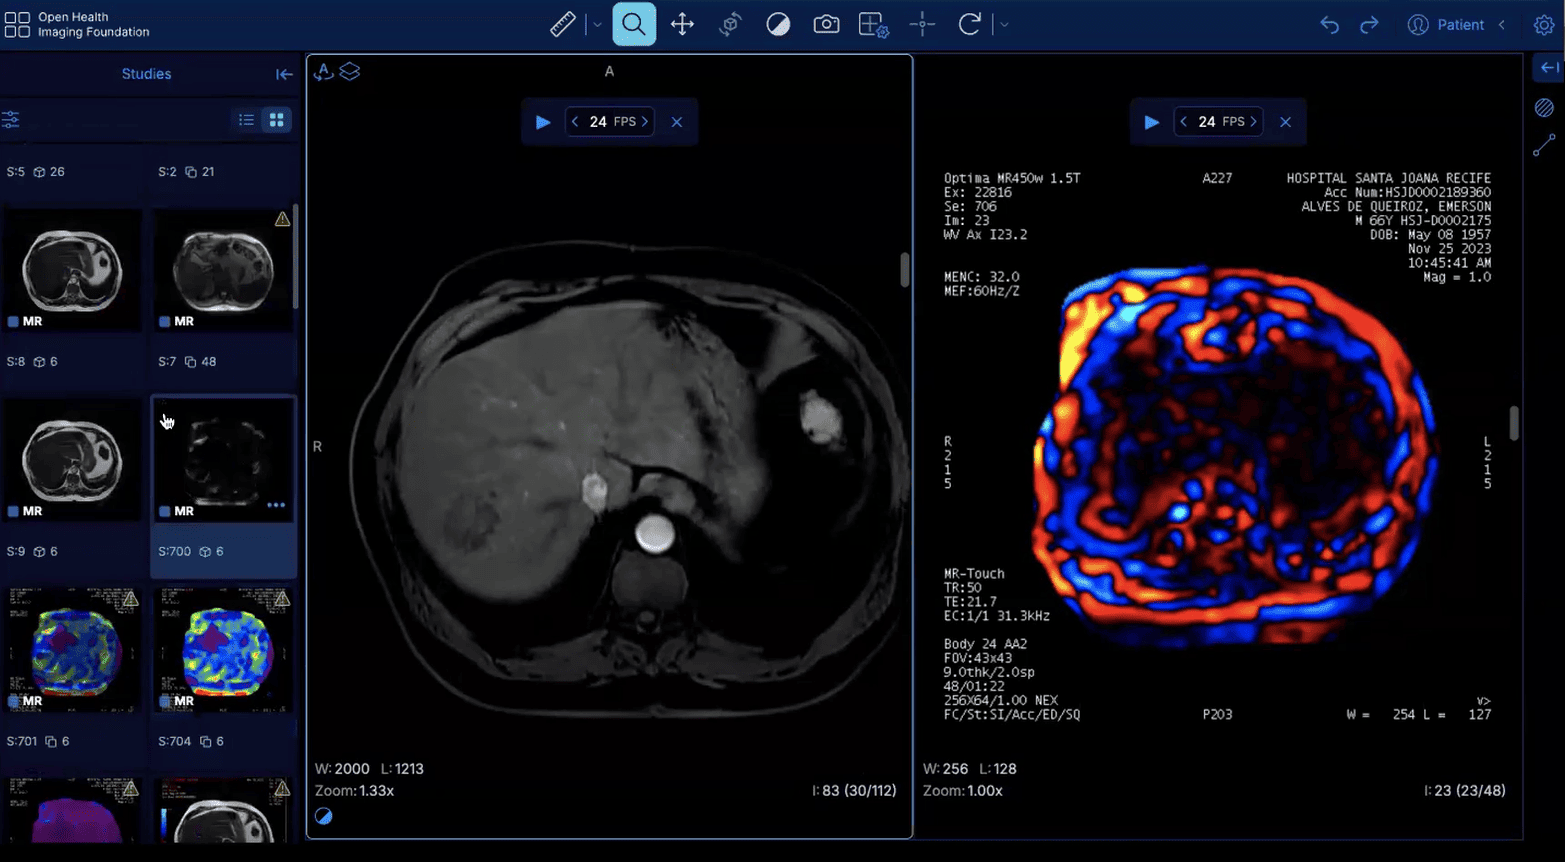

Acesse um PACS com exames reais selecionados para treinar raciocínio diagnóstico como na rotina de um grande serviço de referência.